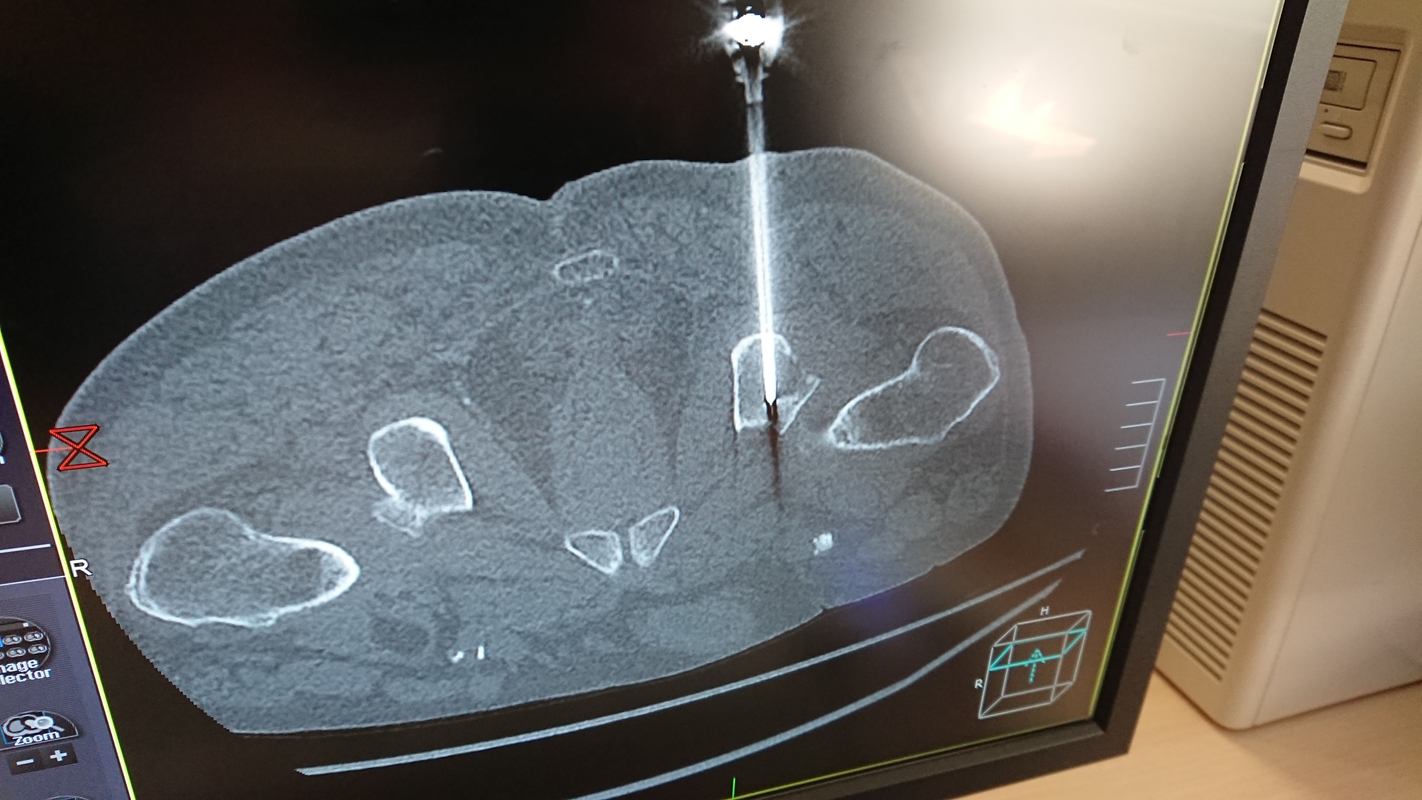

Neurochirurginiam pacientui, nuskausminimo tikslais, Mindaugas Lesutis atliko nervinės šaknelės blokadą stuburo tarpslankstelinėje angoje, o praėjusią savaitę Respublikinėje Klaipėdos ligoninėje pirmą kartą paimta biopsija iš kaulo. Kompiuterinės tomografijos kontrolėje nedidelis kaulo mėginukas buvo paimtas iš įtartino židinio pakitusioje klubo kaulo dalyje. Ši procedūra – minimaliai invazyvi, atliekama vietinėje nejautroje, minimaliais pjūviais, netraumuojant paciento.

„Mes pakankamai dažnai matome pakitimus kauluose, kurių kilmė nėra visiškai aiški ir tik paėmus mėginį galima identifikuoti kas tai per darinys. Tai – vienintelis būdas leidžiantis nustatyti ar darinys yra gėrybinis, ar piktybinis, todėl ši procedūra itin svarbi diagnostikoje“, – sako intervencinis radiologas gydytojas M. Lesutis.

Minėtu atveju nustatyta piktybinio naviko metastazė, kas leis tinkamai įvertinti paciento būklę ir planuoti atitinkamą gydymą.